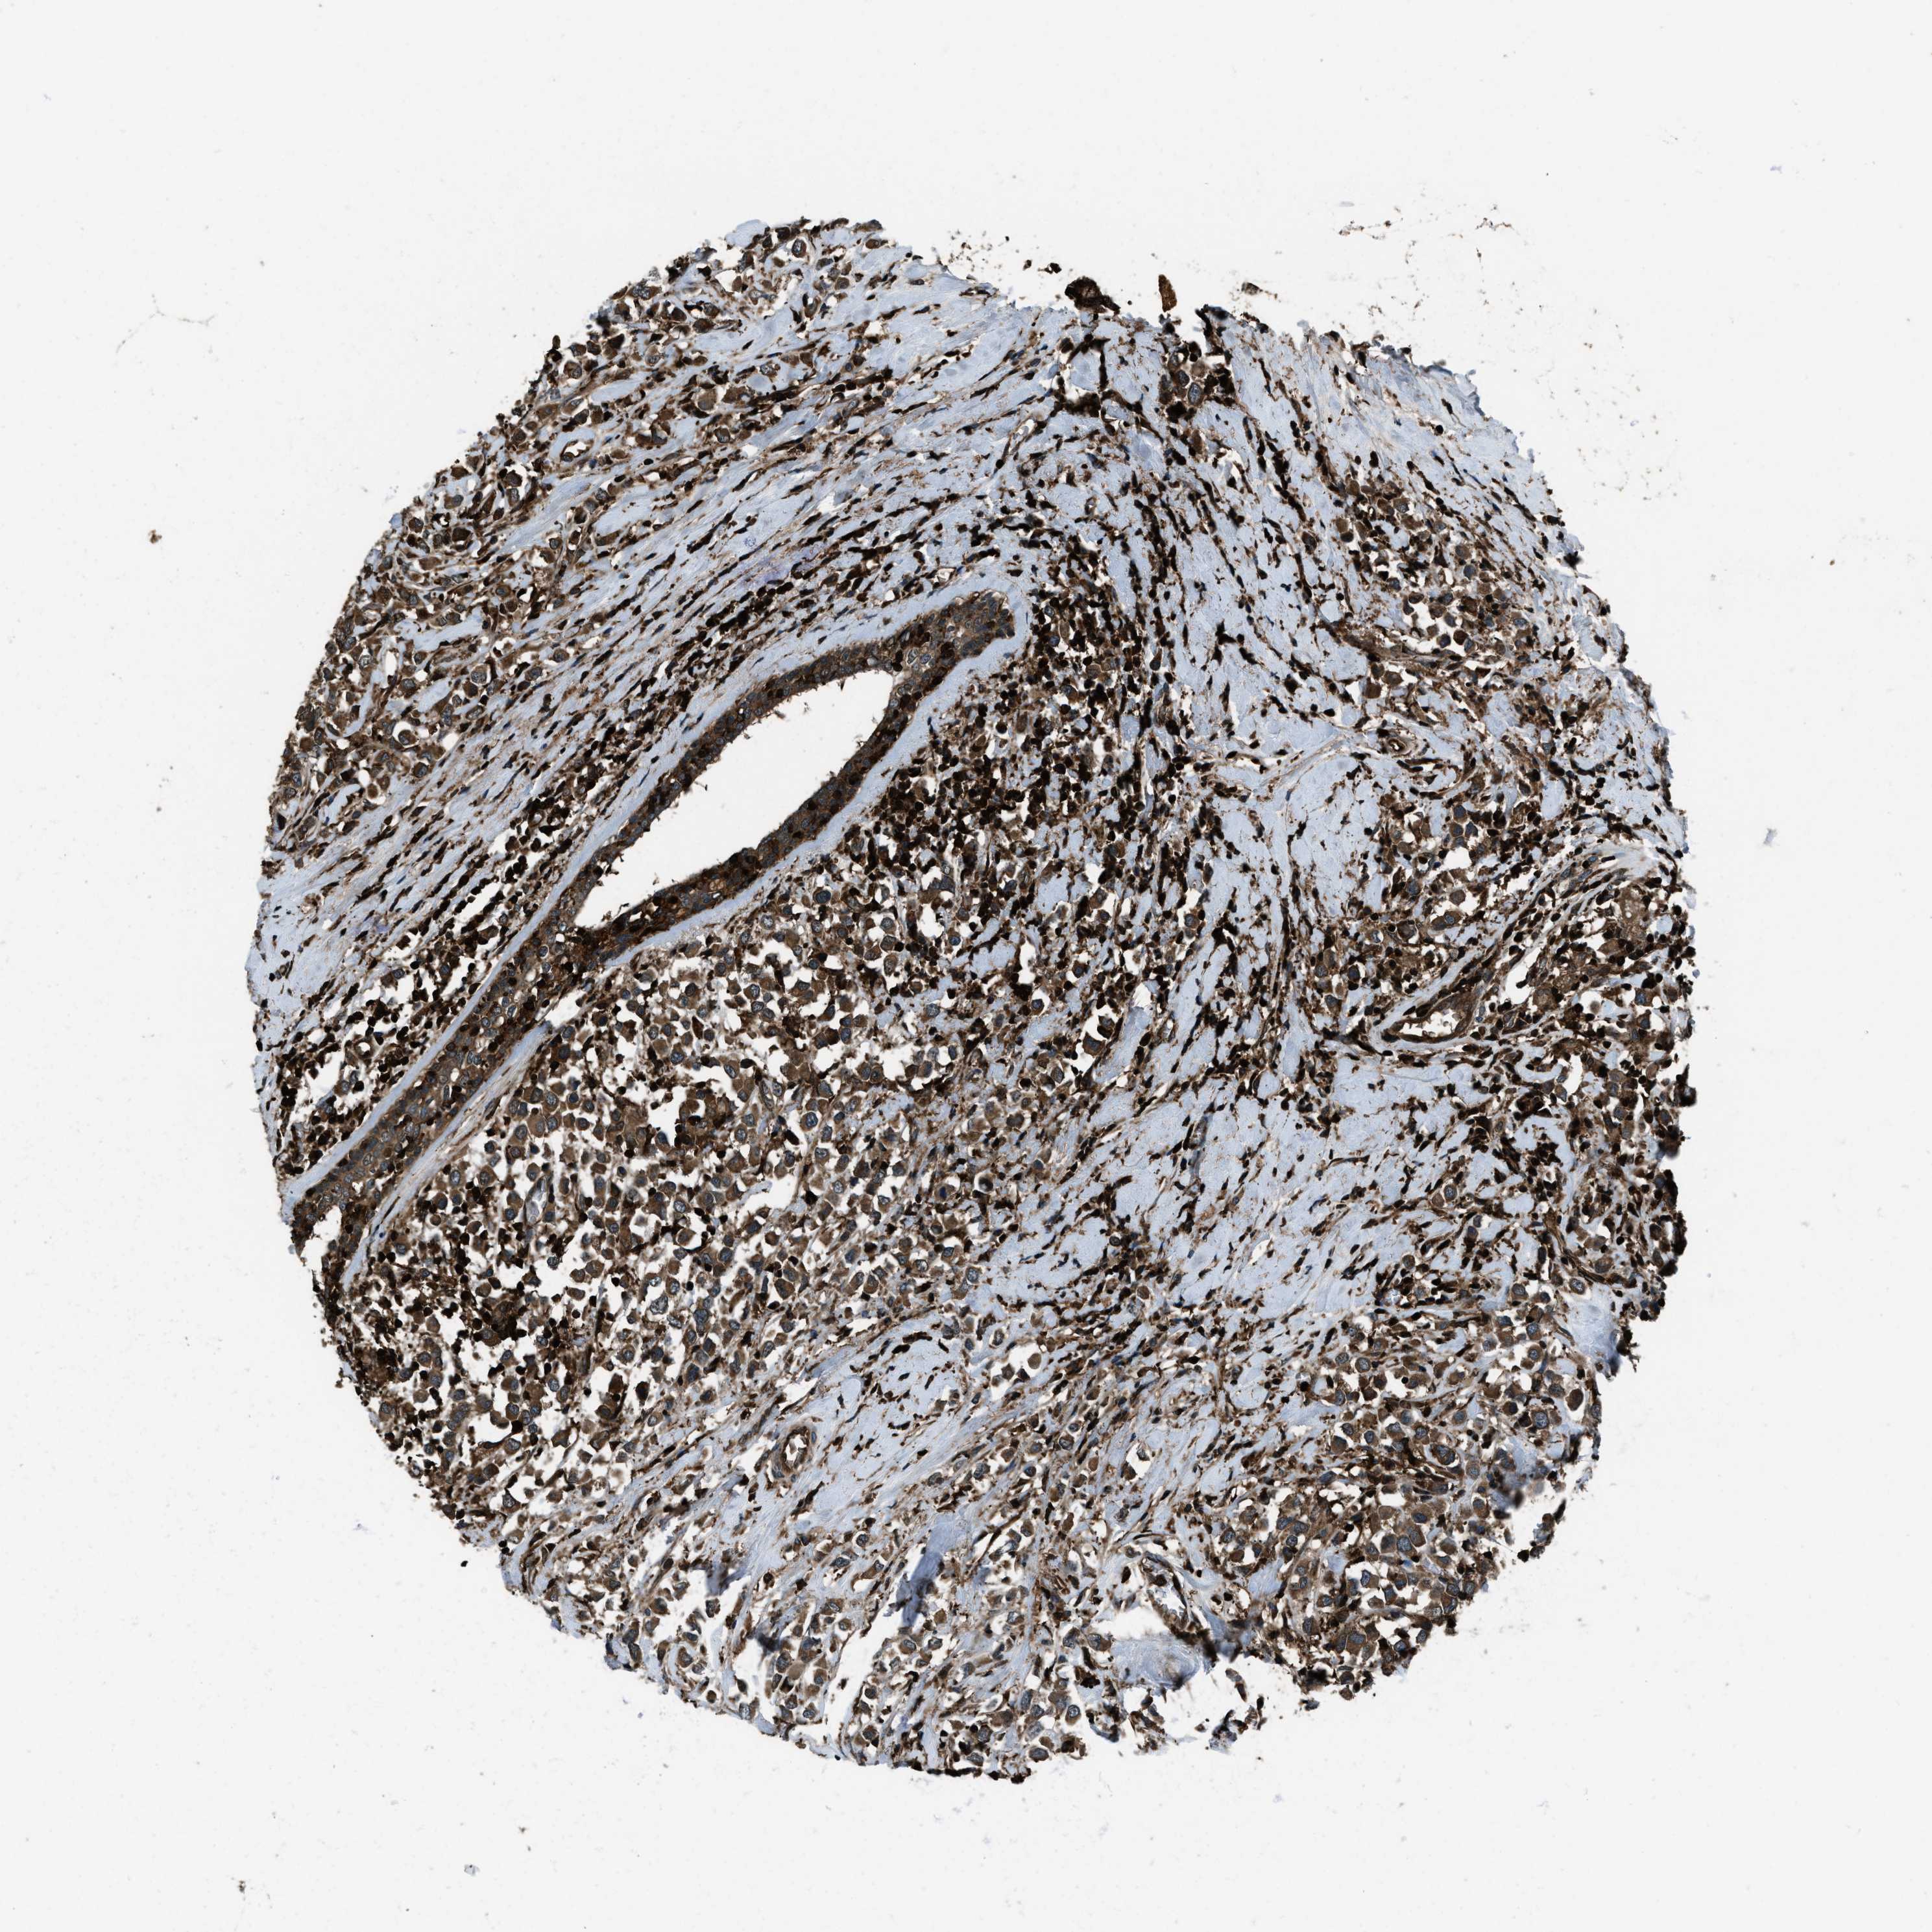

CANCER BREAST CANCER Show tissue menu

BRCA TCGA BRCA VALIDATION PROTEIN EXPRESSION